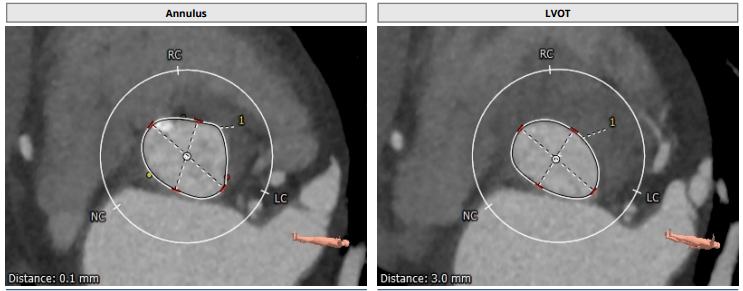

经心尖经导管主动脉瓣置换术治疗极度横位心主动脉瓣关闭不全

极度横位心tavr病例_mmhg_患者_手术